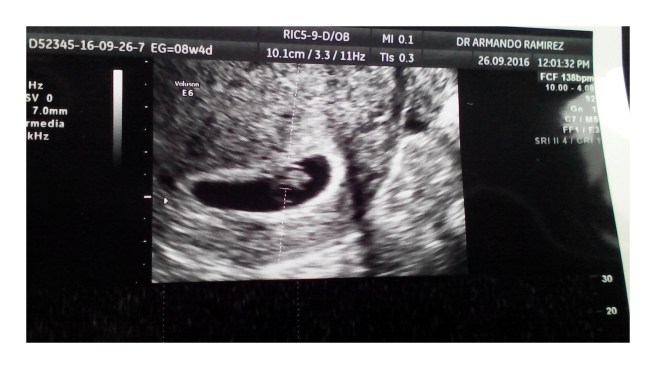

Felices de dar la bienvenida y extender nuestro abrazo hasta el infinito a nuestr@ nuev@ Reynosa Contreras.

Ocho semanas y un corazón que late a toda velocidad.